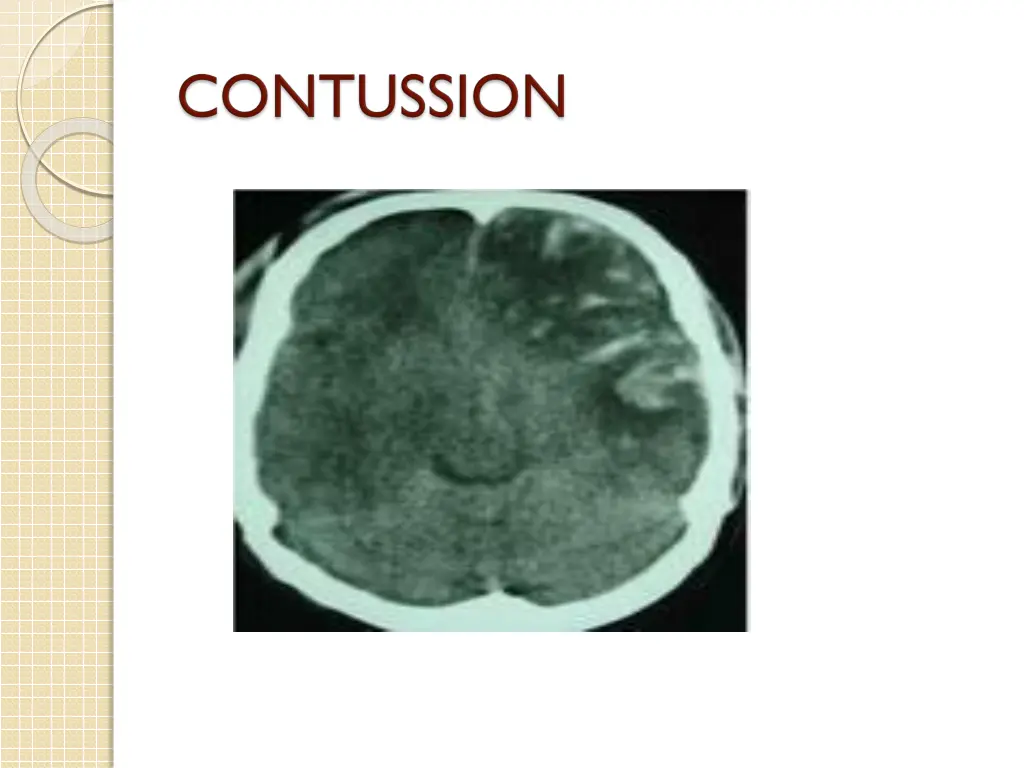

2- focal inj.:defined as visible damage that is generally limited to a well circumscribed region; e.g contusions(coup &countercoup),SDH,EDH,S.A.H,ICH,IVH Occur in half of all pat. With severe brain inj., ,and 2/3 of brain inj.related death.

3-diffuse brain injury.:occur without macroscopic structural damage a-cerebral concussion(transient reversible neurological dysfunc. As a result of trauma ) b-diffuse axonal injury c-ischaemic/hypoxic neuronal damage